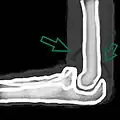

A schematic drawing showing the sail sign which represents an effusion.